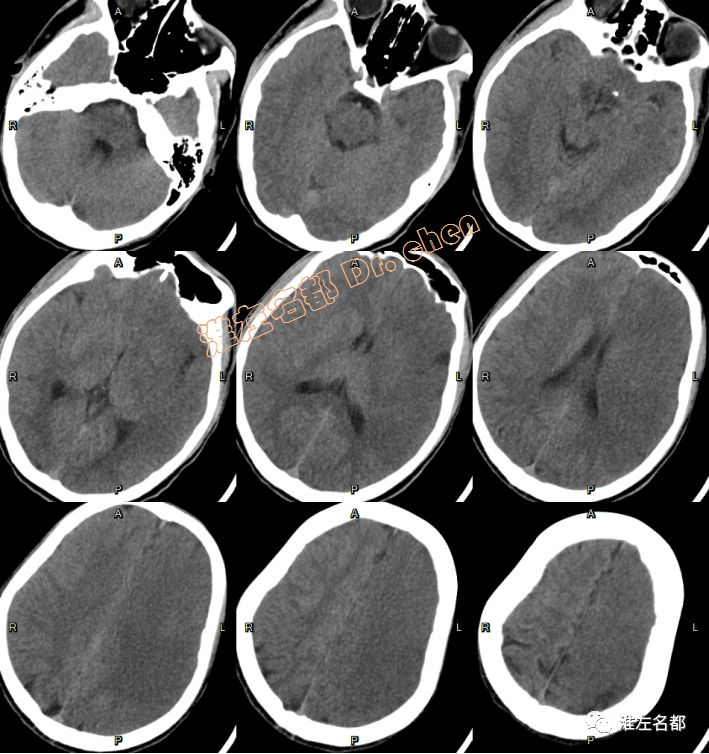

急诊多模式CT

△头颅CT平扫:左侧半球大范围低密度,灰白质分界消失,脑沟受压变小-消失;左侧大脑中动脉区ASPECT-2。

△头颅CTA:左侧颈内动脉末端和大脑中动脉未见显影;左侧颈内动脉显影较右侧细小,造影剂浓度淡(提示血流缓慢)。

△颈部CTA:颈部动脉未见异常。

△脑CTP:左侧半球大范围TTP较对侧显著延长,左侧大脑中动脉上干供血区CBV和CBF显著降低。